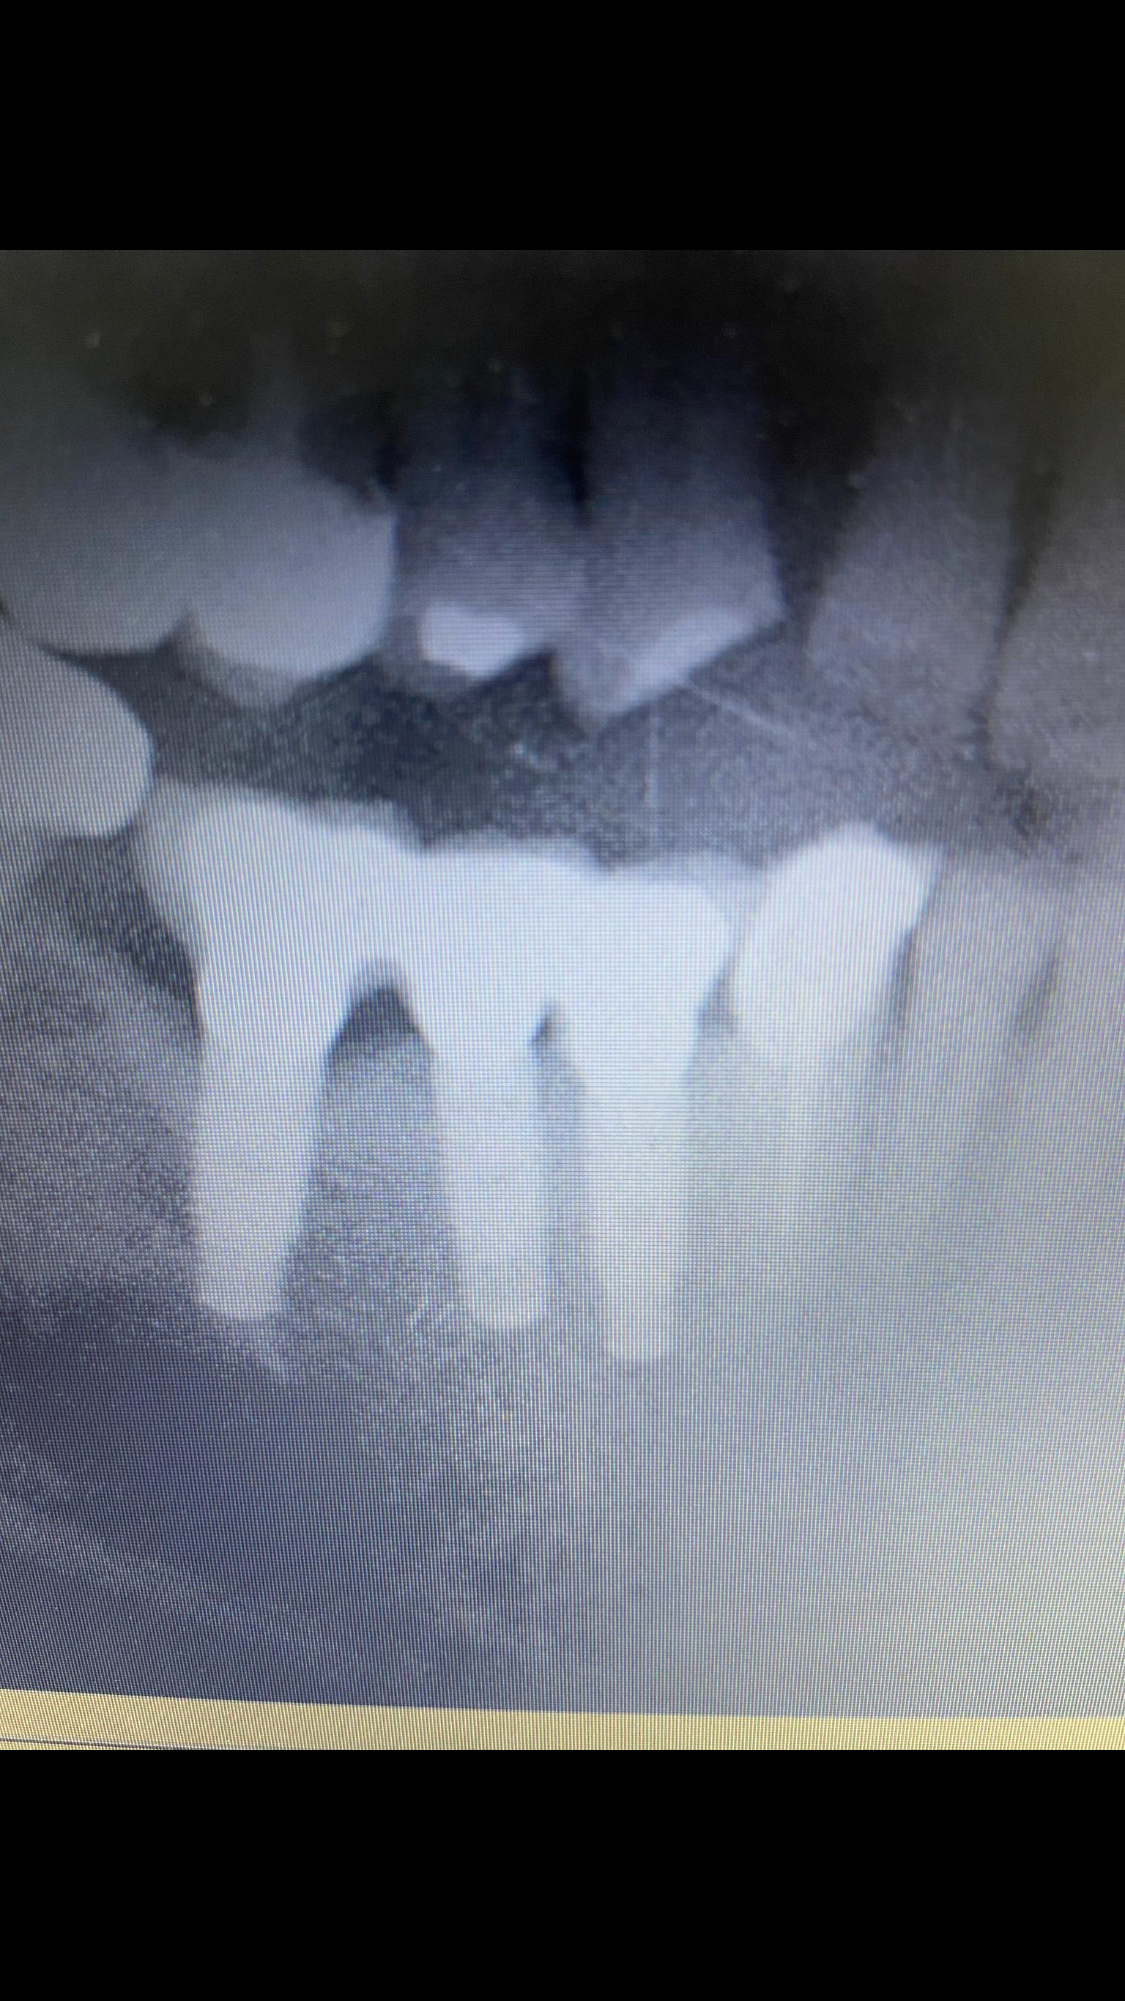

Hola, Me podríais ayudar a determinar el tipo de implante que lleva? las coronas del puente se le aflojan constantemente. Muchas gracias Angela

hola, me ha venido un paciente con este implante colocado hace 6 años. Alguien sabría decirme que marca es? Creo recordar que por dentro tenia una estructura triangular. [...]

Buenos dias necesito saber marca del implante y q es necesario para rehabilitarlo muchas gracias